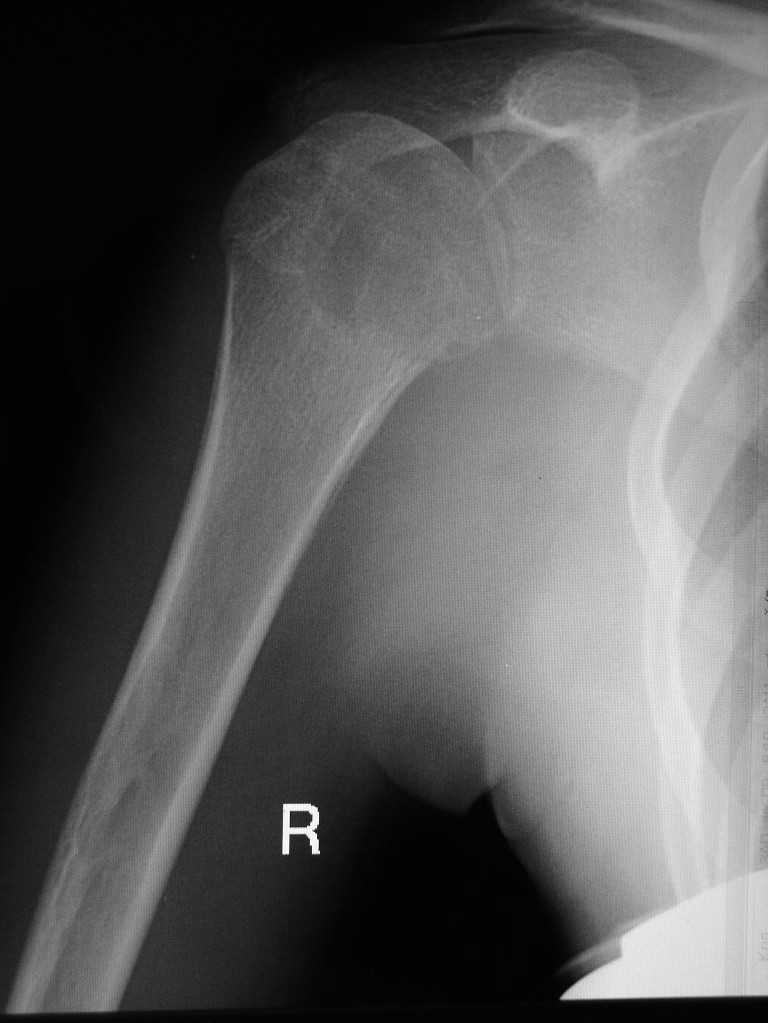

Здравствуйте уважаемые коллеги. Прошу помочь определится с диагнозом. Девушка 16 лет, в

течении 10 мес. беспокоят боли в правом плечевом суставе. Последних два месяца возникло

резкое ограничение подвижности в суставе. Со слов больной и родителей месяц назад проходила

курс лечения у травматолога с диагнозом "периартрит". На момент осмотра плечо отведено до 40

град., активные и пассивные движения резко ограничены, болезненны. Кожные покровы не

изменены, пальпация сустава болезненна, общ. ан. крови - норма. Снимки прилагаю. Заранее

благодарен за помощь.